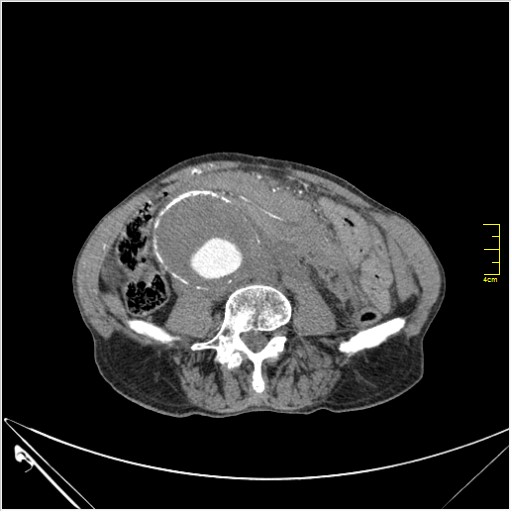

КТ брюшной полости. Мужчина с пальпируемой опухолью в животе

Пациент Т. 64 года, обратился на КТ брюшной полости амбулаторно (!), по направлению семейного врача с диагнозом abdominal mass, буквально: образование брюшной полости.

ТУберкулез позвоночника с обширной деструкцией и с натечником (Вообще-то, я КТ не занимаюсь. Была бы УЗ картинка...)

Huge abdominal aorta aneurism. Simple renal cortical cysts (Bosniak type 1).